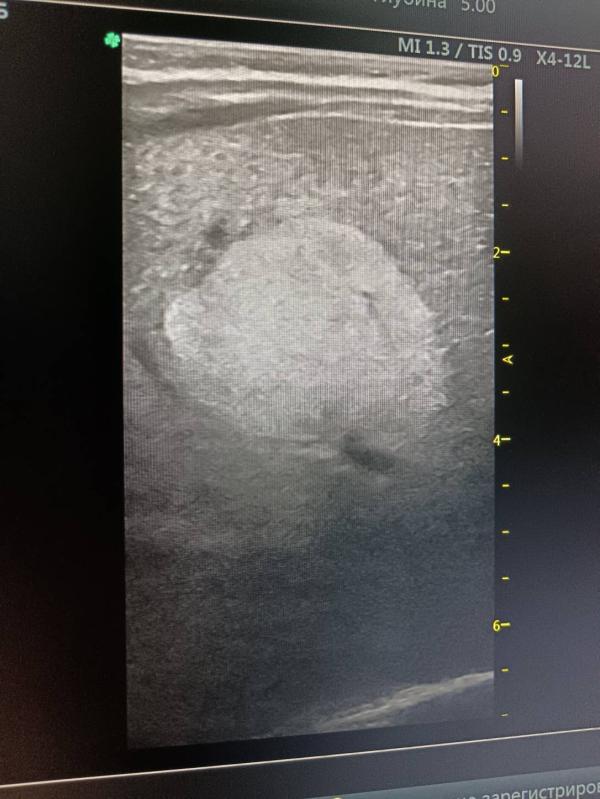

Проходили узи планово, мед осмотр сегодня с малышом. Обнаружили образование в печени, не киста, почти 3 на 3 см, с кровотоком и не ровными краями. Врачи испугались, отправили не ждать, ехать в больницу в Саратовскую областную в хирургич отделение. Там нам сказали, что у них нет лицензии на детей до 4 мес, нам отказали в госпитализации. Перенаправили в 3 советскую, там тоже нас отфутболили, с недовольным лицом. Сказали, что такими вопросами занимается зав отделения, а он будет только в понедельник и у нас случай гн экстренный, ждите понедельника. Я просто в шоке... Что это за образование не сказали. Но я поняла что все серьёзно по реакции врачей... Что делать с этим всем не знаю... Теперь ждать понедельника, звонить в 3 советскую, написала 2 врачам хирургам из Москвы, но ответ ждать не известно сколько... Я в растерянности 😭

Выглядит как типичная капиллярная гемангиома, не переживайте сильно, при впервые выявленном всегда настораживаются и обследуют тщательно чтобы исключить плохое

@alexsabelaya09, может да ,от отца предрасположенность. По эхограммам не вижу страшных признаков

Выглядит реально не очень. Размер, неровные контуры и кровоток пугает. Отпишитесь потом что это. Здоровья вам 🙏🙏